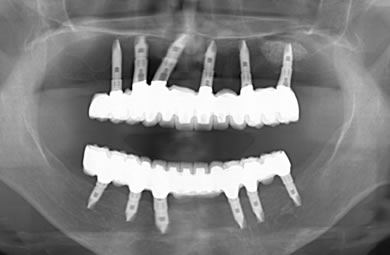

インプラントの症例写真 IMPLANT

骨再生スピードインプラント治療+AGC連結セラミック治療

| 治療内容 | インプラント12本(サイナスリフト+GBR+抜歯即日スピードインプラント+遊離歯肉移植)、AGCハイブリッドセラミック連結ブリッジ2装置(上顎・下顎)、テンポラリーインプラント2本 | ||||||||||||||||||||||||||||||||